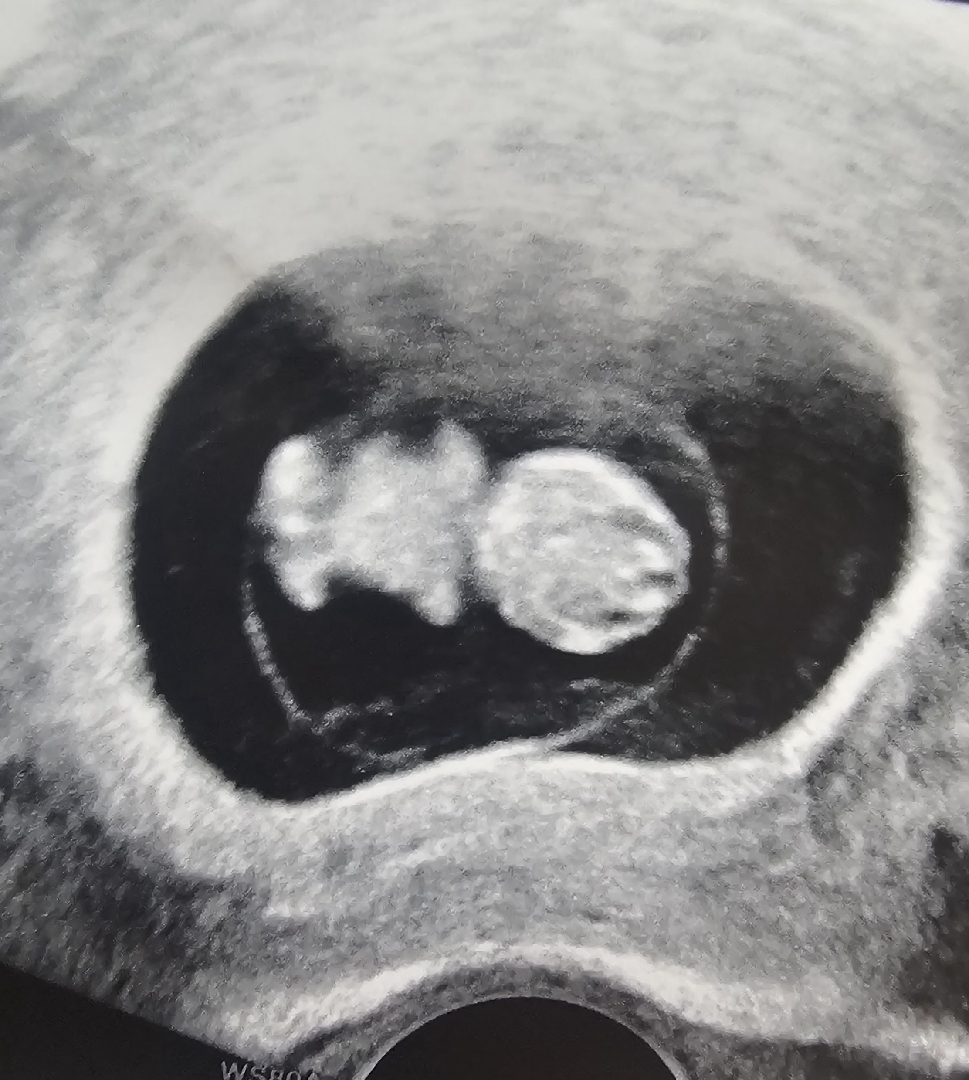

오늘 딱 9주차! 젤리곰이 꼬물꼬물 움직이는 거 보고 왔네요. 넘넘 귀여워요❣️